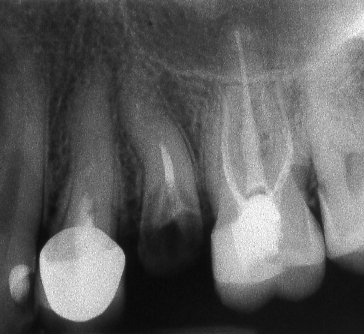

Ендодонтията е раздел от съвременната дентална медицина, който раздел изучава физиологията и патологията на вътрешната част на зъба - пулпна кухина и коренови канали. Названието на раздела идва от старогръцки - ендос - представка за вътрешност и одонтос - зъб. Това е една от научните дисциплини, които претърпяха голямо развитие през последното деситилетие.